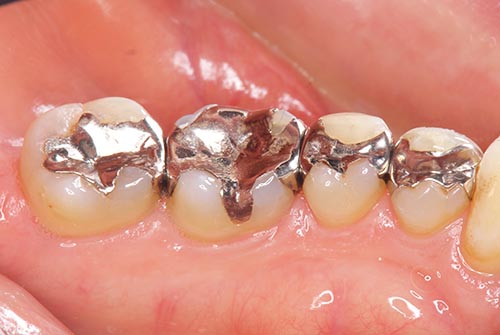

詰め物が多い方の特徴

詰め物が多い=虫歯になりやすいになります。虫歯になりやすい方は、何が原因でなりやすいのか?を明確にする必要があります。時間(歯を磨く時間、食生活、習慣)・遺伝(歯の質)・糖分(摂取量)・細菌(虫歯菌の数)この4つが組み合わさって虫歯になりますので、自分の原因は、何なのか?を明確にして虫歯予防をする必要があります。

詰め物が多いということは、やはり、歯のクリーニングの間隔も普通の方よりも短めにする必要があります。通常の方よりもリスクが高いことを自覚しましょう。患者さんの中には、虫歯を治せば歯医者に通わなくても良いと思われている患者さんがいらっしゃいますが、そうではありません!定期的に歯科医院にてクリーニングを受けることは、必要最低限の歯の予防となり、日々のブラッシングが1番の予防になります。

では詰め物が多い方のおすすめクリーニングは、詰め物と歯の隙間のチェックと他に虫歯ができないようなクリーニングとフッ素コーティングがおすすめになります。また、歯ぎしり・食いしばりが原因で詰め物が多くなっている方は、歯と歯の間を中心にクリーニングを行うのがおすすめになります。写真のように歯と歯の間にまたがる詰め物が多い場合は、間違いなく歯ぎしり・食いしばりですので、ナイトガードの作製と噛み合わせのチェックもクリーニングと同時に行ってもらいましょう。